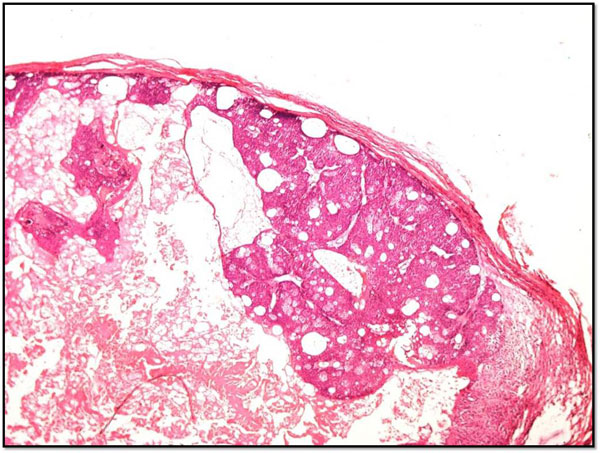

Muir-Torre syndrome is an autosomal dominant disease characterised by multiple sebaceous carcinomas and visceral malignancies, particularly colonic carcinoma. The sebaceous carcinomas in such patients show cystic change, and this is deemed to be a virtually diagnostic feature (see figure below). It is important to recognise this disease, as it has implications for genetic testing and screening of family members.

cystic sebaceous carcinoma